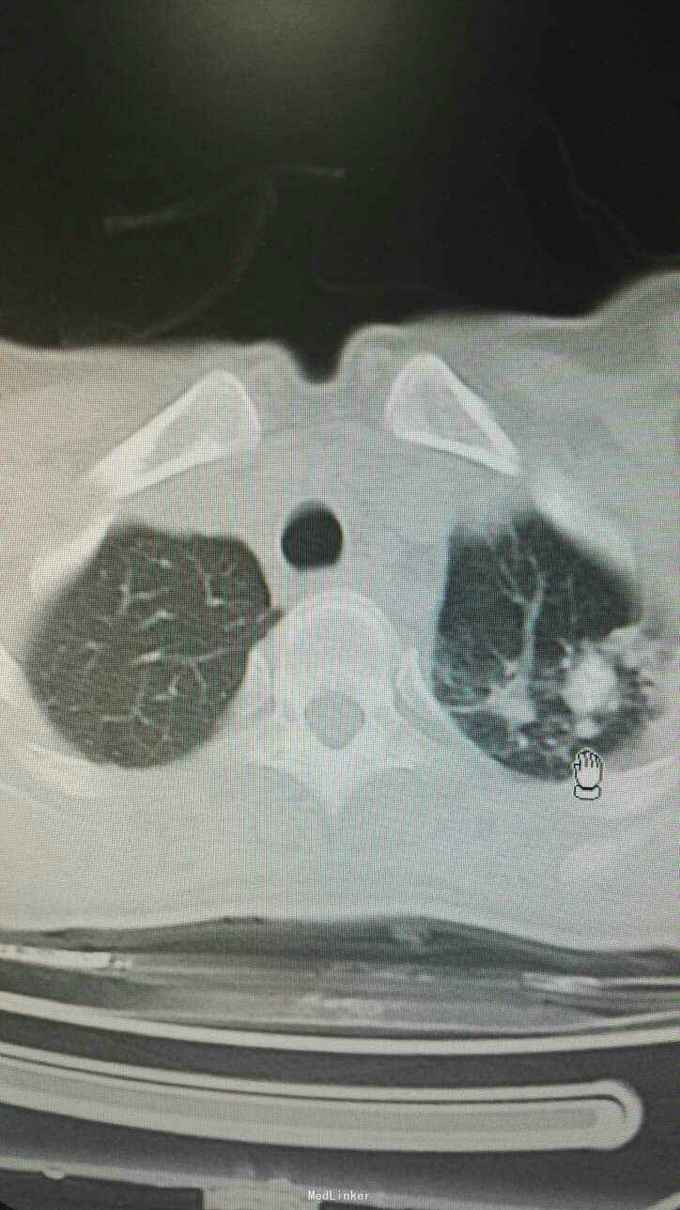

体温38.9℃,心率103。双肺呼吸音粗,未闻及干湿性罗音。心率快,律齐。腹无特殊。右下肢小腿肿胀,见外伤陈旧淤斑。胸部CT示双肺多发病灶,双上肺病灶考虑陈旧性结核,余病灶考虑感染?肿瘤?

入院诊断肺多发病灶查因:肺梗死伴感染?结核复发?肺癌?入院予抗感染,抗凝等治疗。查肿瘤指标,风湿指标未见异常,因甲亢未控制未行CT增强,行右肺病灶活检,未见肿瘤及肉芽肿,见较多坏死物。住院联合抗感染及抗凝,对症治疗后,患者发热胸痛症状好转。

患者体温正常,无明显胸痛。患者既往有下肢血栓病史,且肺病灶多在靠近胸膜处,胸痛明显,与血管分布一致,最后诊断考虑肺梗死伴感染。